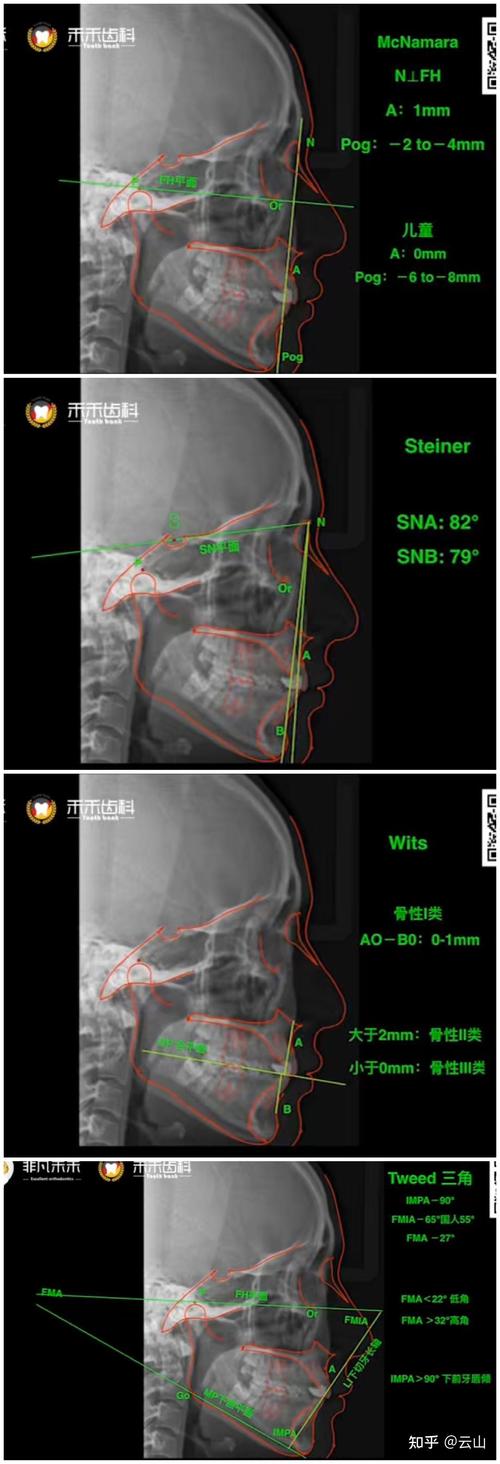

z角的测量基于头颅侧位片,首先需确定两个关键标志点:鼻根点(N)和软组织颏前点(Pgs),鼻根点为额骨与鼻骨的交界处,是侧位片正中矢状面上最前凸的点;软组织颏前点则是下唇与颏部皮肤轮廓的交界处,代表颏部软组织最前点,连接N与Pgs即可得到“审美平面”,该平面被视为面部侧貌的参考基准,随后,需识别上唇突点(Ls)和下唇突点(Li),分别指上、下唇皮肤轮廓曲线的最前凸点,通过测量Ls和Li到审美平面的垂直距离(以毫米为单位),即可得到上、下唇的z角值:距离为正值表示唇部位于审美平面前方(唇突),负值表示唇部位于审美平面后方(唇缩)。

z角的正常值范围因种族、年龄和性别存在差异,但临床研究普遍认为,上唇z角正常值约为-4.0mm至+2.0mm,下唇z角约为-2.0mm至+4.0mm,白种人上唇z角平均值为-1.2±2.1mm,下唇为1.8±2.3mm;而亚洲人群可能因面部骨骼结构差异,上唇z角偏小(更接近负值),提示唇部相对后缩的可能性较高,值得注意的是,z角并非孤立指标,需结合骨性因素(如下颌平面角、ANB角)、牙性因素(如前牙突度、覆覆盖)以及软组织厚度(如上唇厚度、颏部厚度)综合分析,以全面评估患者的侧貌特征。

影响z角的因素主要包括骨性支撑、牙齿位置和软组织张力,骨性方面,上颌骨前突或下颌骨后缩会导致唇部代偿性前突,z角增大;反之,下颌前突或上颌后缩可能使z角减小,牙性因素中,上前牙前突会直接推上唇前移,增大上唇z角;而前牙内收不足则可能导致唇部回缩不明显,z角改善有限,软组织方面,上唇过厚或颏部后缩会使唇突点相对前移,影响z角准确性;唇肌功能异常(如口呼吸导致的上唇紧张)也可能在测量时导致唇突点位置偏移,需在自然放松状态下拍摄头颅侧位片以减少误差。